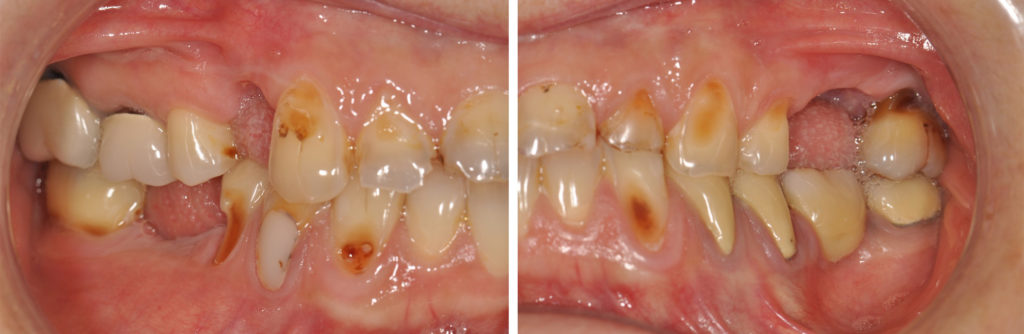

Fig. 2a à 2f : vues intra-buccales de la situation initiale

Analyse dentaire :

• les dents 14, 25, 26, 36 et 46 ont toutes été extraites pour des raisons de délabrements des tissus dentaires (et non pas pour des raisons parodontales),

• les dents 17 et 16 sont dévitalisées et porteuses de coiffes céramo-métalliques dont les limites vestibulaires sont exposées. La dent 36 est remplacée par un bridge céramo-métallique de 4 éléments en appui sur les dents 34, 35 et 37 (dévitalisées),

• les dents 11, 22, 27, 44, 45 et 47 présentent des obturations coronaires en composite qui présentent des signes d’infiltration,

• toutes les les autres dents présentent des signes d’érosion avancée avec des plages d’exposition dentinaires, larges par endroit, vestibulaires, linguales et/ou occlusales.

Analyse parodontale :

On ne note pas de signes – ni cliniques, ni radiologiques – de maladie parodontale (pas de poches, pas de mobilités…).

Le biotype parodontal est fin. On note des récessions gingivales sur les dents et dont certaines sont très proches de la ligne de jonction muco-gingivale. L’alignement des collets des incisives maxillaires est asymétrique.